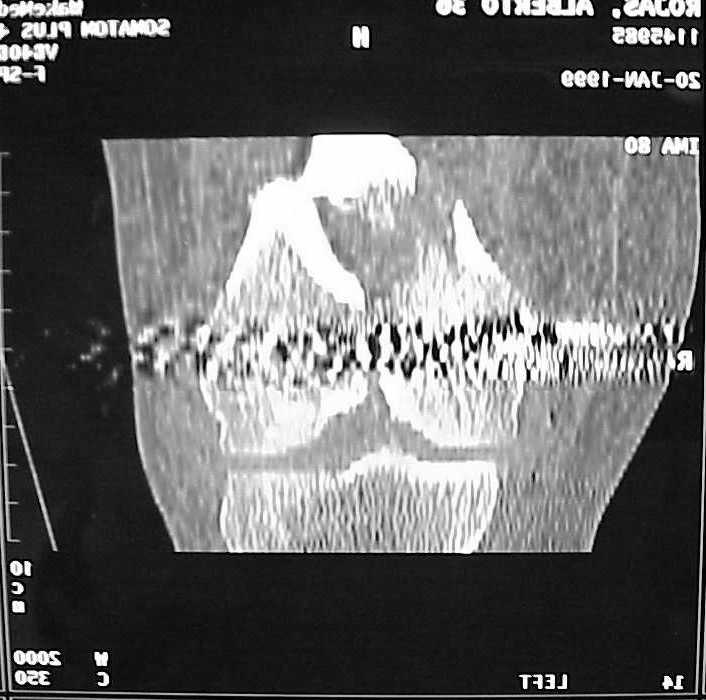

A CT and knee xrays would help identify lateral condyle comminution and/or a "hoffa fragment" of the posterior condyle. I am concerned that the lateral cortex is not sufficient to give purchase for a retrograde IMN. blocking screws could improve this as a possibility. A long blade or LISS if avaible would be my secondary choices. Good luck. Any chance you can get these cases transferred earlier when it

Lateral condyle looks too small for the blade, and the plate too short.

Use 6.5 mm cannulated screws if you have and

place one anterior to where IMN will go if anterior cortex if insufficient and AP screws on either side of the IMN out of the trochlea to provide some additional varus/valgus stability. I worry about the leg going into valgus w/the lack of lateral cortex.

See attached case that was done several years ago before LISS. He had comminuted trochlea and anterior blocking screws were used to prevent anterior IMN cut-out.